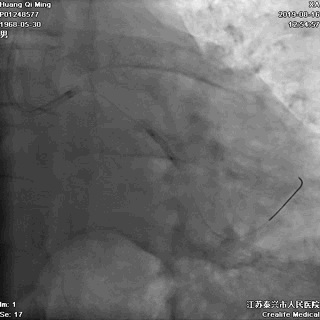

2.0*25 药物洗脱球囊,8atm*60秒释放药物

2.5*25 药物洗脱球囊,8atm*60秒释放药物

术后即刻效果满意